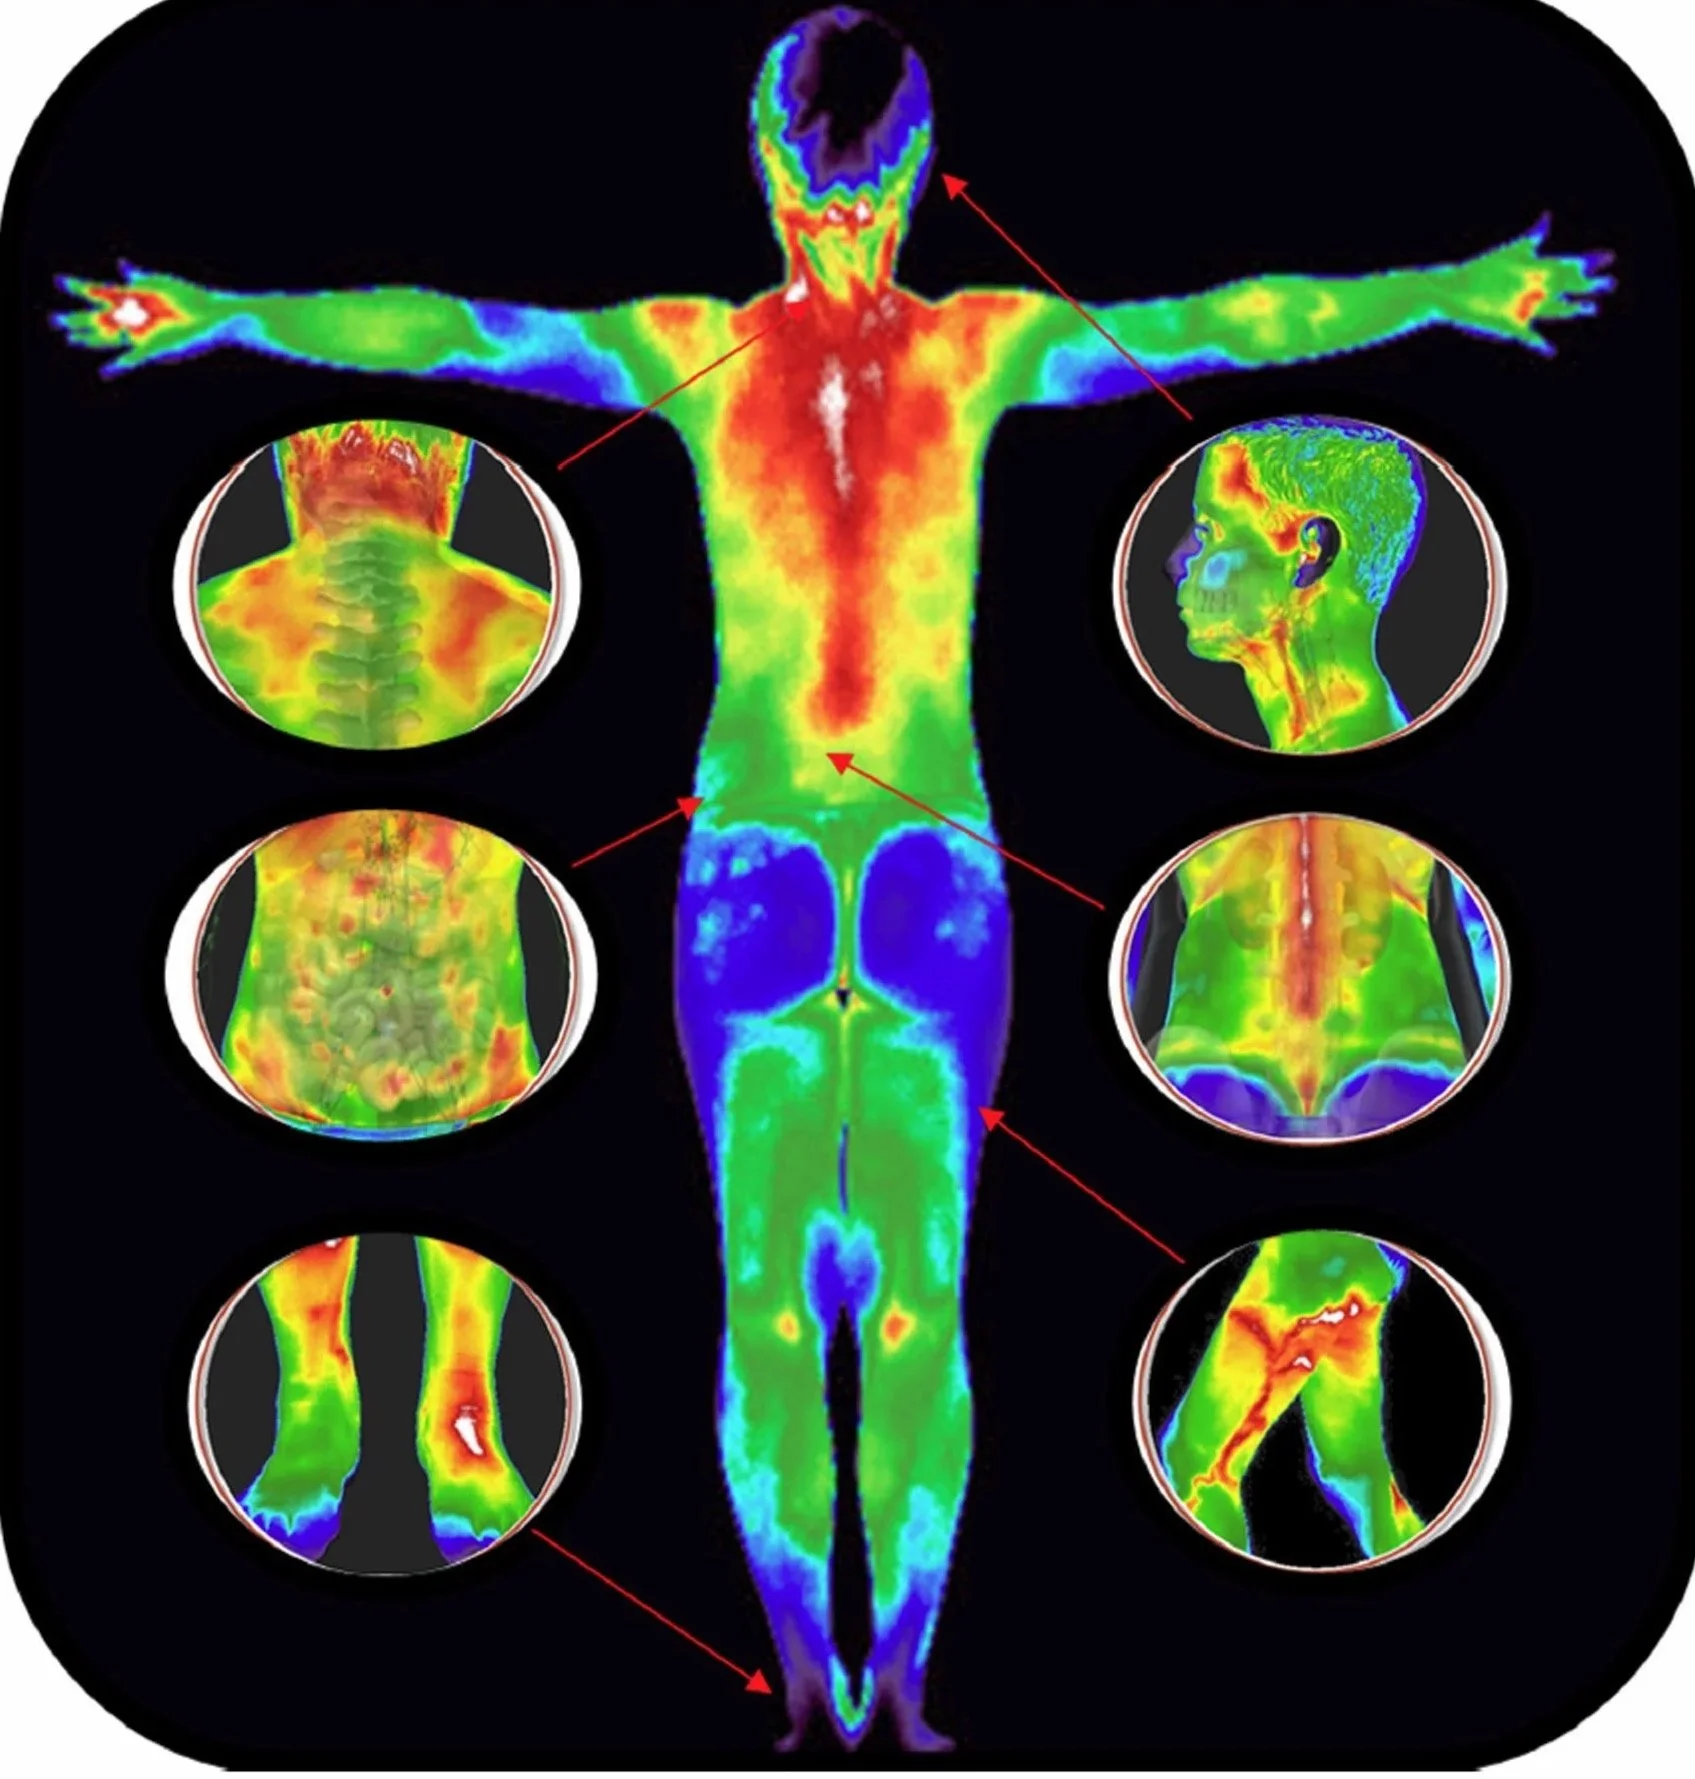

Thermography is a non-invasive, painless and contactless imaging technology that uses infrared cameras to detect subtle temperature variations in the body.

These thermal patterns can highlight inflammation, poor circulation, and early signs of dysfunction.

Infrared images to discover inflammatory patterns. Upper Body includes: Head, Neck, breast/chest, Trunk, Upper Back, Hands, and Shoulders. Lower Body Includes: Lower Back, Abdomen, Hips, Knees, Legs and Feet.

Infrared images to discover inflammatory patterns for the head, neck, breast/chest, abdomen, trunk, upper/lower back, shoulders, arms, hands, hips, knees, legs, and feet.